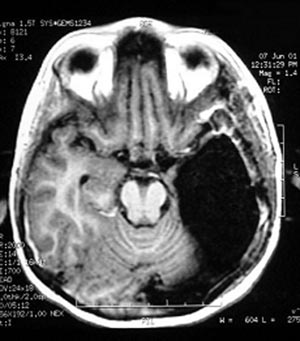

Figura 68 - Ressonância nuclear magnética pós-operatória mostrando adequada ressecção da lesão.